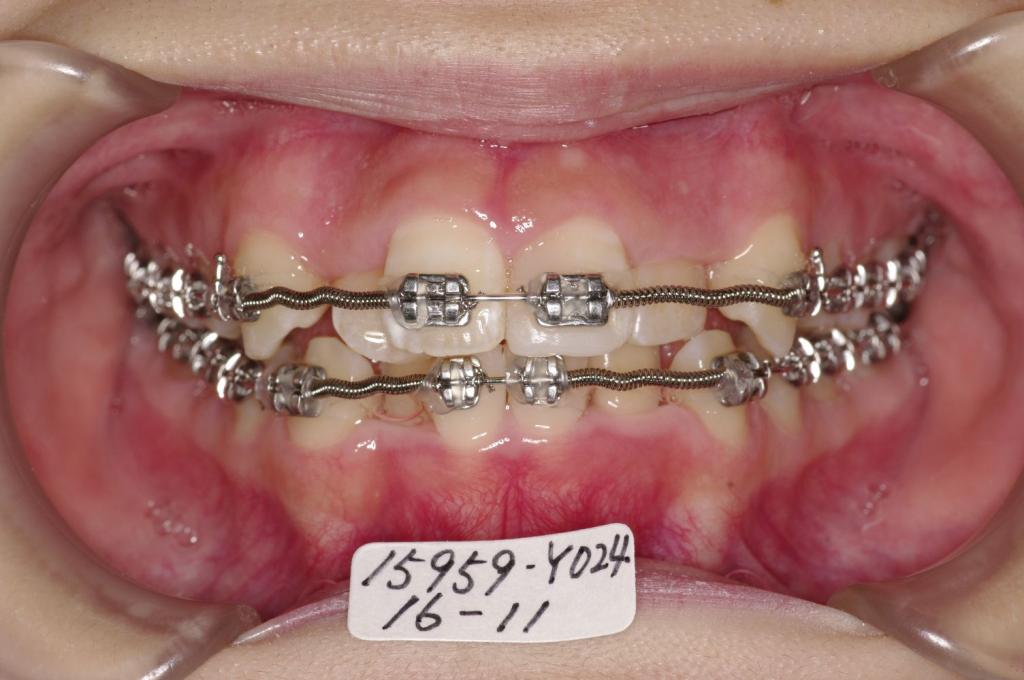

- 前歯の重なり